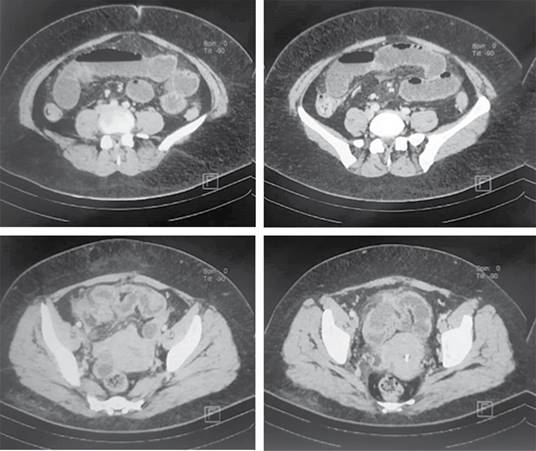

Paciente femenino de 47 años sin antecedentes no patológicos de relevancia. Tabaquismo a razón de 20 cigarros al día con índice tabáquico de 25, el cual se considera riesgo intenso para enfermedad pulmonar obstructiva crónica (EPOC); cesárea electiva hace 13 años. Inicia su padecimiento cuatro días previos a su valoración, al presentar dolor en epigastrio de intensidad 7/10 sin irradiaciones, sin desencadenantes, ni exacerbantes; acompañado de náusea y vómito en cinco ocasiones de contenido gastro-alimentario. A las 24 horas de inicio del cuadro, refiere automedicación e ingesta de butilhioscina 10 mg cada 12 horas, tras lo cual presenta leve mejoría, por lo que deja a libre evolución. A las 48 horas presenta aumento de vómitos, así como migración del dolor hacia fosa iliaca derecha, no refiere fiebre. Acude a particular a las 72 horas de inicio del cuadro, donde se administra tratamiento antibiótico con amikacina, analgésico y metoclopramida a dosis no especificadas, sin ceder el cuadro, por lo que acude a hospital particular al aumentar intensidad de dolor abdominal, en donde se le realizan estudios de laboratorio, los cuales muestran: leucocitosis de 23.3 × 10e3/μl a expensas de neutrófilos (19.48 × 10e3/μl), el resto de resultados de laboratorio sin alteraciones. Del mismo modo, al sospechar cuadro de apendicitis aguda, se solicita TC toraco-abdomino-pélvica contrastada, la cual se reporta con probable apendicitis aguda complicada con absceso localizado, así como hallazgos de broncograma aéreo y datos sugestivos de neumonía atípica por SARS-CoV-2, CO-RADS 4 (Figuras 1 y 2), por lo que deciden envío a urgencias de nuestra unidad.

Figura 1: Tomografía axial computarizada de abdomen, no se visualiza apéndice cecal; sin embargo, se observan asas de íleon distal con engrosamiento mural e inflamación de la grasa mesentérica de fosa iliaca derecha, sugestivos de proceso inflamatorio.